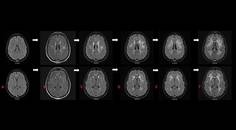

Higher Density of Neurons Discovered in White Matter in Patients with Temporal Lobe Epilepsy

Patients with temporal lobe epilepsy have a higher density of neurons in the arch- and neocortical white matter, according to a new study. In an effort to characterize these neurons and investigate their distribution in mesial temporal sclerosis, researchers found that both excitatory and inhibitory cells were present among these neurons and that a subset of neurons in the white matter was Tbr-1-immunoreactive; these neurons coexpressed NeuN and neurofilament marker SMI311R. No co-localization of Tbr1 was observed with the inhibitory neuronal markers, calcium-binding proteins. “We suggest that a large population of white matter neurons comprises remnants of the subplate,” the investigators wrote. “Furthermore, we propose that a subset of white matter neurons was arrested during migration, highlighting the role of cortical maldevelopment in epilepsy associated with mesial temporal sclerosis.”

—Neuroscience. 2016 Oct 1;333:140-50.